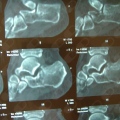

- Cirurgia do Joelho

Fotos

Artroscopia

Artroscopia Cirurgica Do Joelho

R. Dr Bacelar 173,cjt 61, São Paulo

R$ 10.000

Consultório particular. Dr Jorge Sayum Filho

Artroscopia do ombro

Enxertia Autologa Osteocondral (Mosaicoplastia) Ou Condral

Meniscectomia

Reconstrução ligamentar intra-articular do joelho (Ligamentoplastia)

- Cirurgia do Joelho